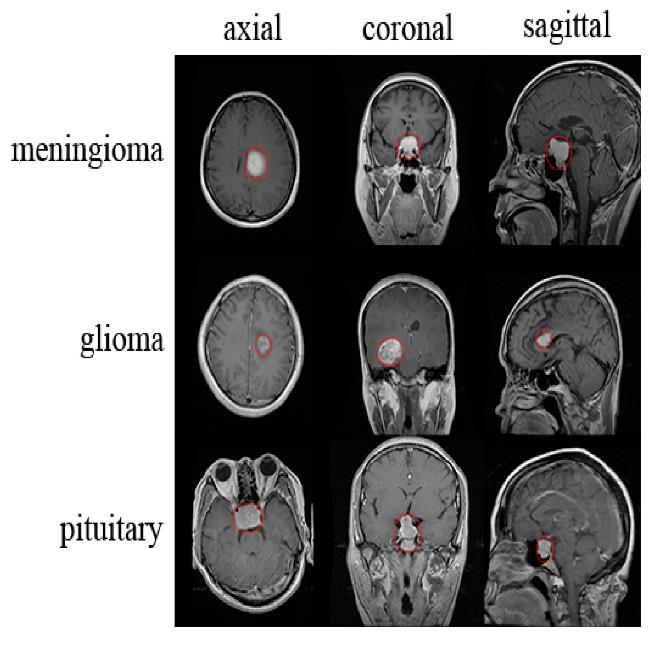

brainthatresemblesafibrousweb.Approximately3,540 children under the age of 15 are diagnosed with brain tumors this year. It is crucial to have a proper understanding of braintumorsand their stagesinorder to prevent and treat the illness. An abnormal mass of tissue in which cells grow and multiply uncontrollably, seemingly unchecked by the mechanisms that control normal cells, is called an intracranial tumor, or brain tumor. Although there are over 150 distinct types of brain tumors known to exist, primary and metastatic brain tumors are the two main categories. Tumors that arisefrom thebrain'stissuesorthe brain'ssurrounding tissuesarereferredtoasprimarybraintumors.Primary tumors can be classified as benign or malignant, glial (made up of glial cells) or non-glial (developed on or in thebrain'sstructures,suchasnerves,bloodvessels,and glands).Tumorsthatoriginateinotherpartsofthebody, like the breast or lungs, and spread to the brain, usually via the bloodstream, are referred to as metastatic brain tumors. Metastatic tumors are malignant and categorizedascancer.Thetypesoftumorsareshownin Fig1.

Fig 2, images are collected from KAGGLE websites related to brain tumors such as Glioma tumor, Meningioma tumor, Pituitary tumor and No tumor. And thenperformpreprocessingstepssuchasnoiseremoval using median filtering algorithm. Finally select the pretrained model such as YOLOV11 model. Based on tumorclassification,calculatetheperformancesystemin termsofaccuracyandconfusionmatrix.Intestingphase, input the brain image and perform classification using best model file. Finally predict the tumors and provide theprecautiondetails